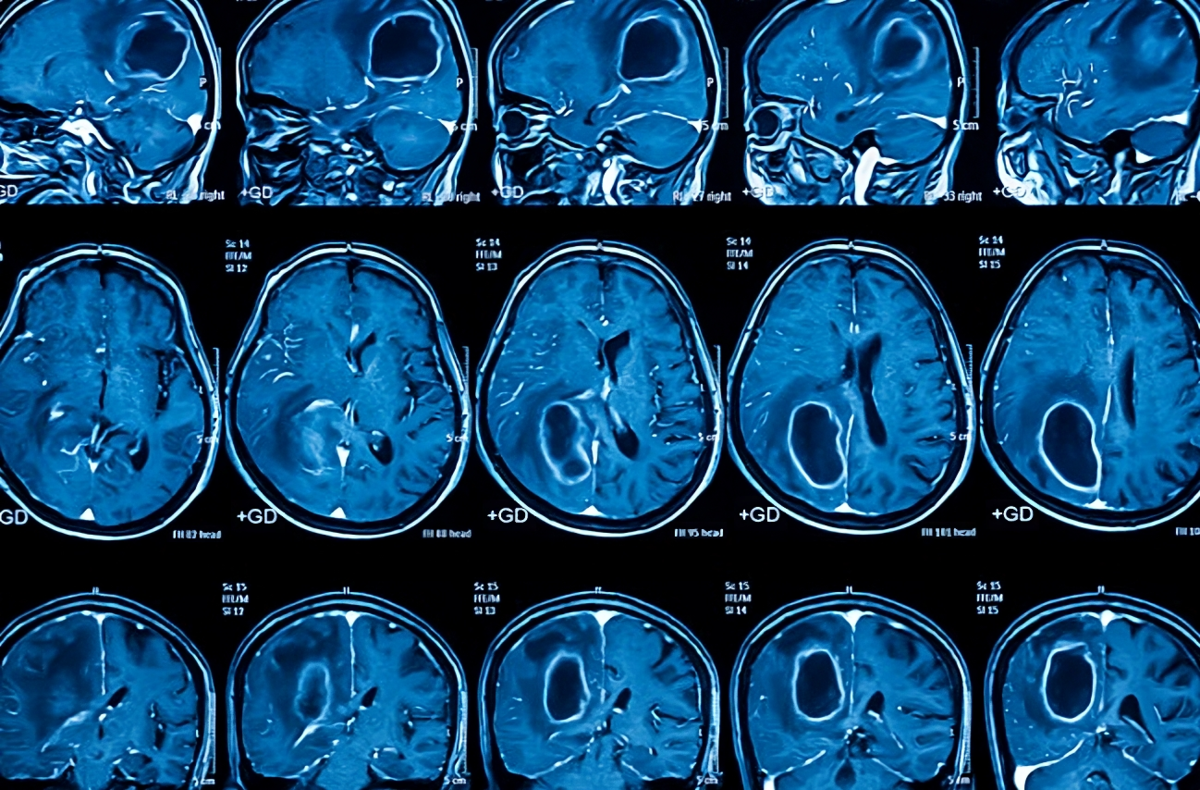

Рак может поражать любую часть тела и давать разные симптомы, в зависимости от типа и стадии рака. Существует более 200 разных типов рака, которые классифицируются по тканям или органам, из которых они происходят. Например, рак кожи — это рак, который возникает из клеток кожи; рак легких — это рак, который возникает из клеток легких и т.д. Разные типы рака имеют разные причины, факторы риска, способы диагностики и лечения.